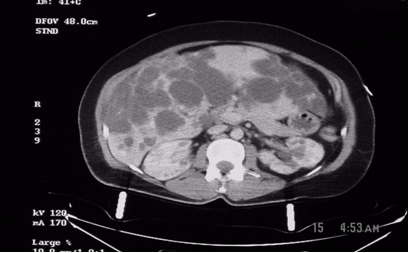

Figure1: These are two contiguous computerized axial tomographic sections of the abdomen obtained after intravenous infusion of contrast.They show an enlarged liver that contains multiple cysts ranging in size from a few to several centimeters, diffusely spread throughout the organ. The kidneys also contain several (>5 total, bilaterally) similar though much smaller cysts but they are not very large. The pancreas, at least to the naked eye, is spared. There are no other obvious abnormalities; the lady, fortunately, had no significant intra-abdominal injuries from her trauma.

Radiologic diagnosis: Autosomal Dominant Polycystic Disease (ADPD).